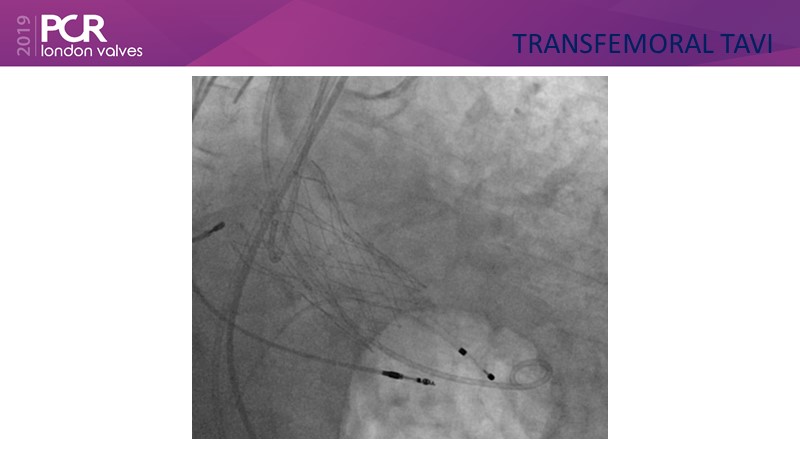

Transfemoral TAVI access using intravascular lithotripsy in patients with challenging peripheral vascular disease

Watch this session to appreciate why it is better to tackle difficult transfemoral access rather than considering alternative access strategies and understand how intravascular lithotripsy mitigates procedural risk.

- To appreciate why it is better to tackle difficult transfemoral access rather than considering alternative access strategies